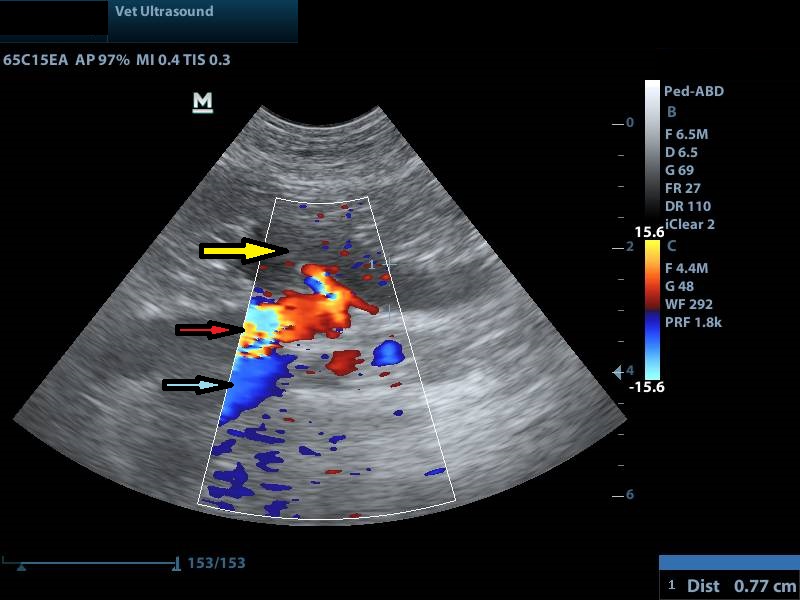

κίτρινο βέλος: έντονη διάταση του ουρητήρα

κίτρινο βέλος: διάταση του αριστερού ουρητήρα

κόκκινο βέλος: κοιλιακή αορτή

μπλε βέλος: οπίσθια κοίλη φλέβα